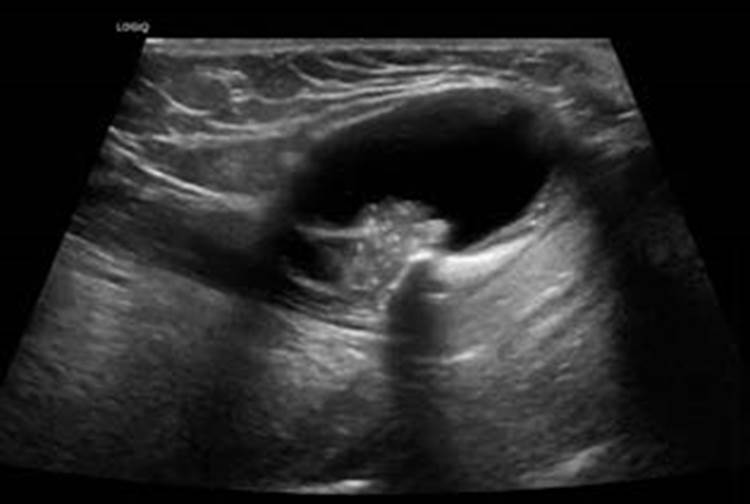

Cervical ultrasound demonstrated a 4 x 3 cm mainly cystic lesion, consistent with a thyroglossal duct cyst (TGDC), presenting focal solid areas with microcalcifications. Contrast-enhanced computed tomography (CE-CT) showed the lesion located in front of the hyoid bone, with upward extension into oral cavity, and revealed an enhancing mural nodule. These characteristics raised suspicion of malignancy, specifically for papillary carcinoma due to the presence of microcalcifications. A fine needle aspiration biopsy (FNAB) was performed, which revealed cancerous cells, consistent with TGDC papillary carcinoma.

Cervical ultrasound and CE-CT are fundamental to characterize and adequately stage these lesions. Carcinoma should be considered in TDGC that have a mural nodule or microcalcifications, which correspond to the psammoma bodies seen histologically in papillary carcinomas.5 FNAB is an important tool to evaluate suspicious lesions but has a low sensitivity.4 The diagnosis of TGDC carcinoma can be confirmed in the post-operative histopathological examination.1

Figure 1: Thyroglossal duct cyst papillary carcinoma. A cervical ultrasound scan shows a cystic lobulated lesion, located anterior to the hyoid bone, with a hyperechoic solid lesion with microcalcifications inside